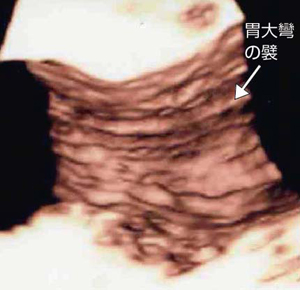

東芝メディカルシステムズ社の「AplioXG」に搭載されている4Dコンベックスプローブは,プローブを機械的に一定速度で扇動して三次元データを収集するものであるが,われわれは,主に中心周波数が5.0(ハーモニック表示)MHzのプローブを用いている。リアルタイム性よりも画質が優先されることから,single sweep(sweep angle:60〜75°)でデータを収集し,その後3D画像を再構成する。管腔造影を行った場合はcavity(白黒反転)表示を用いる。図14は正常な胃体部大彎の3D表示,図15は腸閉塞症例における空腸の3D表示であるが,いずれも襞が明瞭に描出されている。

![]() 図14 正常な胃体部大彎の3D画像 |